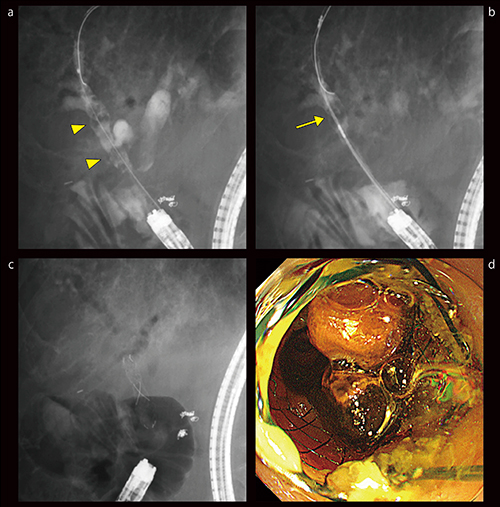

症例3は、89歳、女性、後区域枝(B6)の肝内結石の症例である。MRCPにて結石を認めたものの、本症例は区域性胆管炎のため頻回の入院加療を行っており、胆道気腫もあるため透視上、肝内結石は見えづらいと考えられた。しかし、Ultimax-iでは比較的速やかに後区域枝が造影されて肝内結石が明瞭に描出され、かつ管球を回転させることで後区域枝が長軸に描出されたため(図8 a)、ワイヤの誘導も非常にスムーズに行うことができた(図8 b)。造影像からは結石のあるB6には明らかな狭窄を認めず、バスケットカテーテルやバルーンカテーテルを用いて繰り返し結石除去を行い、肝内結石の透亮像は消失した(図8 c)。術後のMRCPでもB6内の結石の消失が確認された(図8 d)。

図8 症例3:後区域枝(B6)の肝内結石症例(89歳、女性)

a:B6内に複数の肝内結石(▲)

b:ガイドワイヤを誘導

c:バスケットカテーテルで結石除去

d:処置後、MRCPでB6内の肝内結石は消失